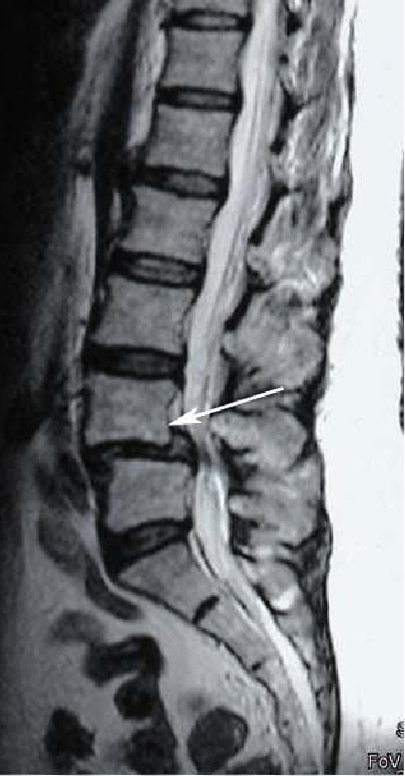

5. Патологический спондилолистез

Патологический спондилолистез встречается при разрушении части позвонка опухолевым или воспалительным процессом. Вовлечение суставного отростка или дужки позвонка в патологический процесс может значительно ослабить позвоночно-двигательный сегмент и привести к смещению позвонка. Остеопороз и другие более редкие заболевания позвоночника могут также привести к спондилолистезу.